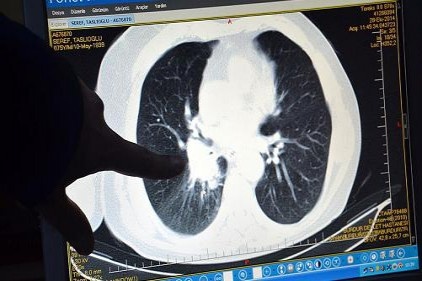

Selçuk Üniversitesi (SÜ) Tıp Fakültesi Dekanı Prof. Dr. Serdar Göktaş, Türkiye'de en sık solunum yolları ve akciğer, kalın bağırsak, mide, pankreas kanserleri ile löseminin ölüme yol açtığını belirterek, "Erkeklerde en sık akciğer, prostat, kalın bağırsak, mesane, mide, kadınlarda ise meme, tiroit, kalın bağırsak, akciğer ve rahim kanseri görülmektedir." dedi.

Dünyada erkeklerde en sık 1,6 milyon kişiyle prostat kanseri görüldüğünü, en çok ölüme ise 1,2 milyon vakayla solunum yolları ve akciğer kanserlerinin yol açtığını ifade eden Göktaş, kadınlarda ise 2,4 milyon vakayla en fazla meme kanserinin saptandığını dile getirdi.

"Ülkemizde en sık solunum yolları ve akciğer, kalın bağırsak, mide, lösemi ile pankreas kanserleri ölüme yol açtı. Erkeklerde en sık akciğer, prostat, kalın bağırsak, mesane, mide, kadınlarda ise meme, tiroit, kalın bağırsak, akciğer ve rahim kanseri görülmektedir." bilgisini veren Göktaş, şunları kaydetti: